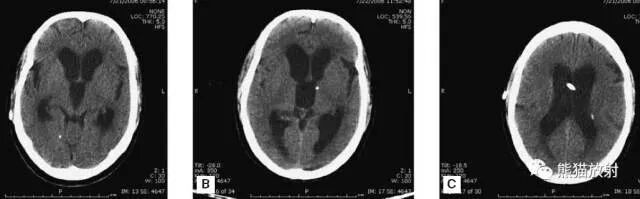

颅脑CT常用的三个窗(图A-C):

- 图A:骨窗(the bone window)

- 图B:脑窗(the brain window)

- 图C:血窗(the blood window)

图A:骨窗;主要用于明确骨折、窦腔病变、颅内积气。

图B:脑窗;可清晰显示灰白质,可发现中风的早期征象或其他导致脑水肿等表现的病变。

图C:血窗;更利于显示硬膜下或颅内出血。

本例表现:骨窗示:右顶骨骨折;三个窗均示:软组织水肿并皮下积气;血窗:少量硬膜下血肿。